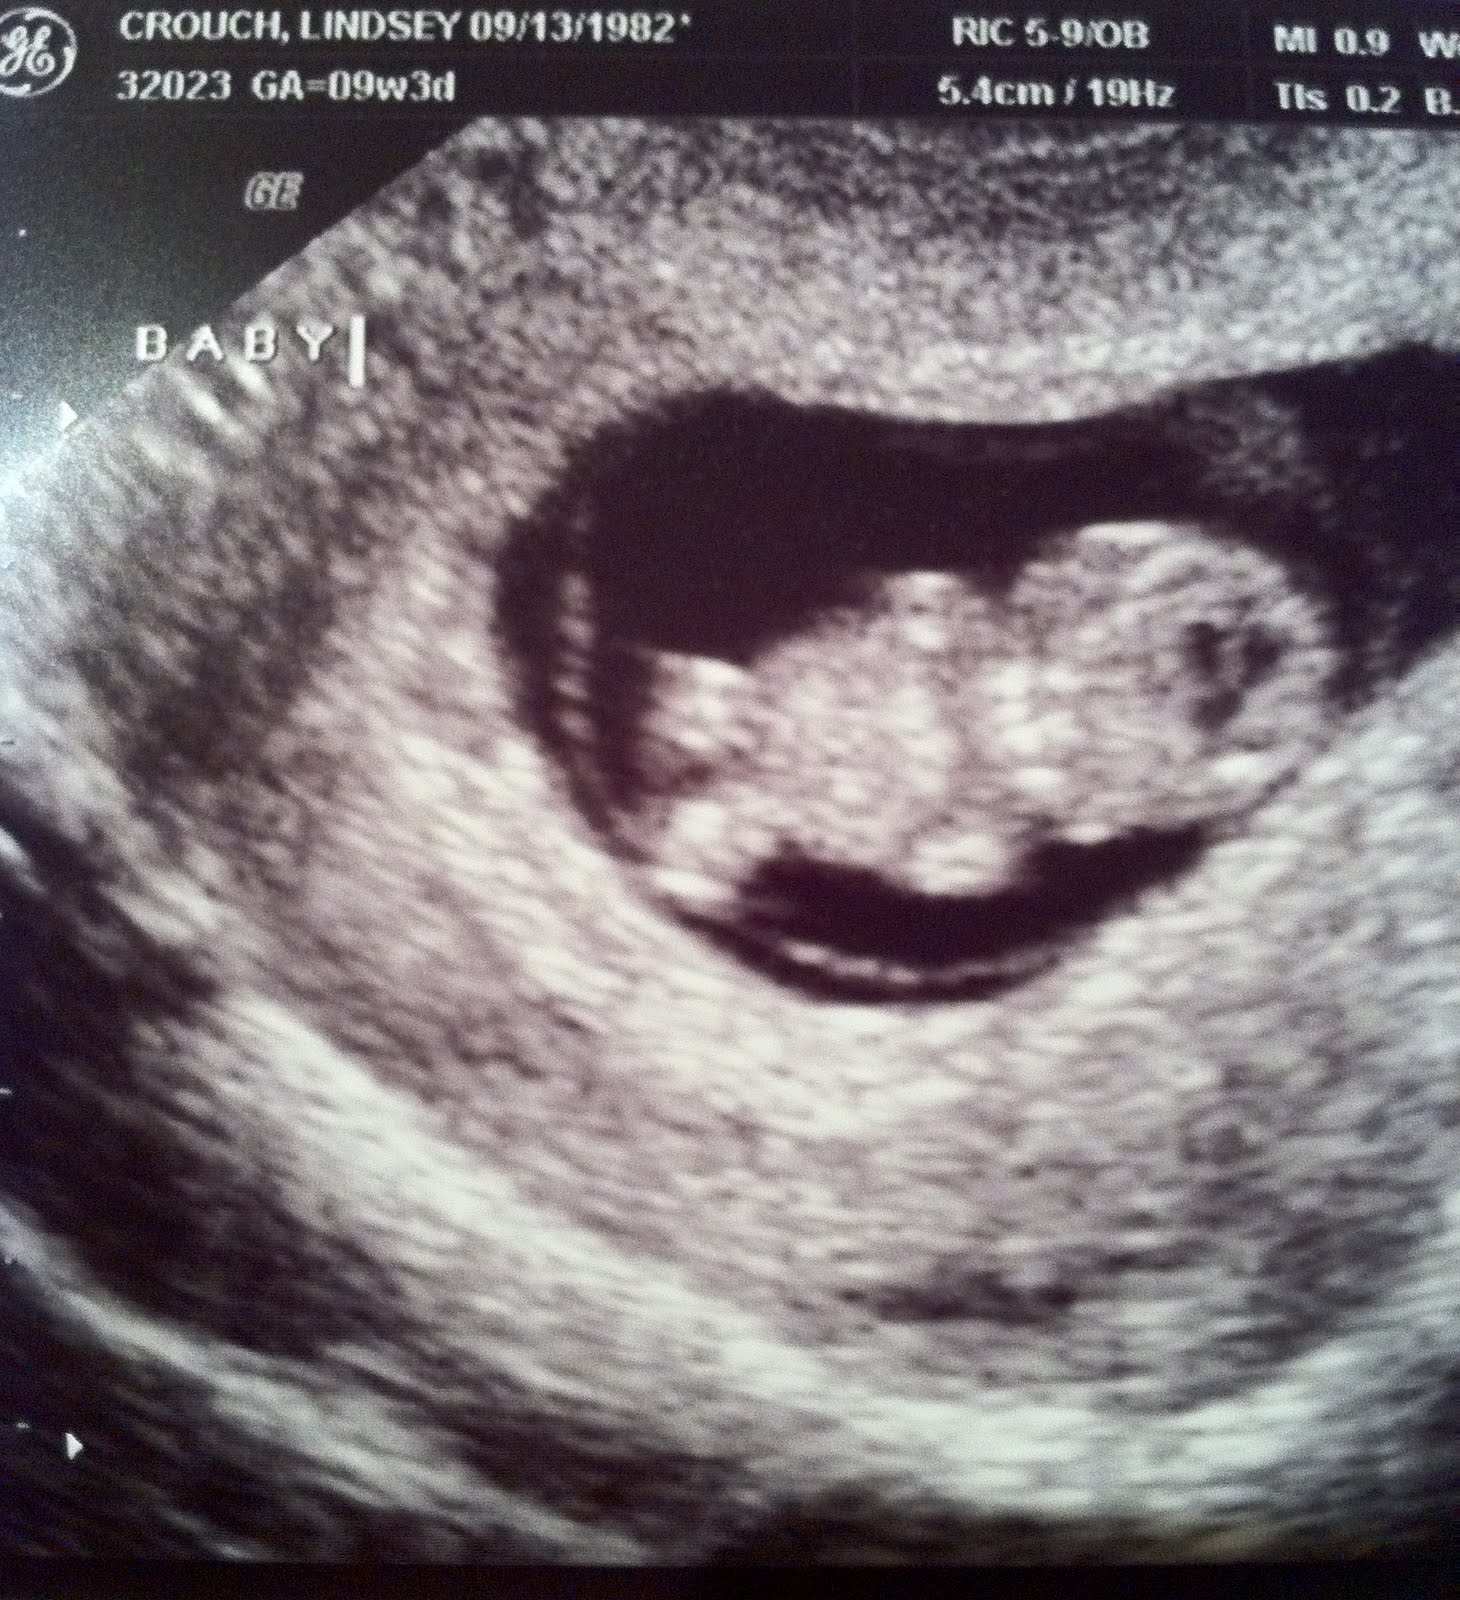

A healthy check up, strong heart beat and two people who have never been more excited in their lives. Look at our perfect little baby...what a sweet little angel.

Now tucking it all away into a special box, because now is not the right time. We have total faith that we will have children in God's time. We so appreciate your cards, loving gifts, notes and emails these past few weeks. They will always be a reminder of your support and love.